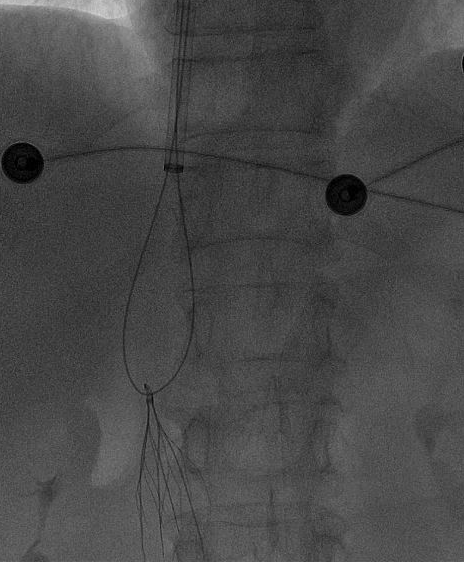

术中,团队在影像设备的精准引导下,娴熟操作介入器械,精准定位倾斜的滤器,避开血管周边组织,逐步完成滤器的调整、抓取与取出操作。

整个手术过程十分顺利,未出现任何血管损伤等意外情况,这枚让阿婆和家属忧心许久的“困难”滤器被成功取出,术后阿婆生命体征平稳,身体状况良好。